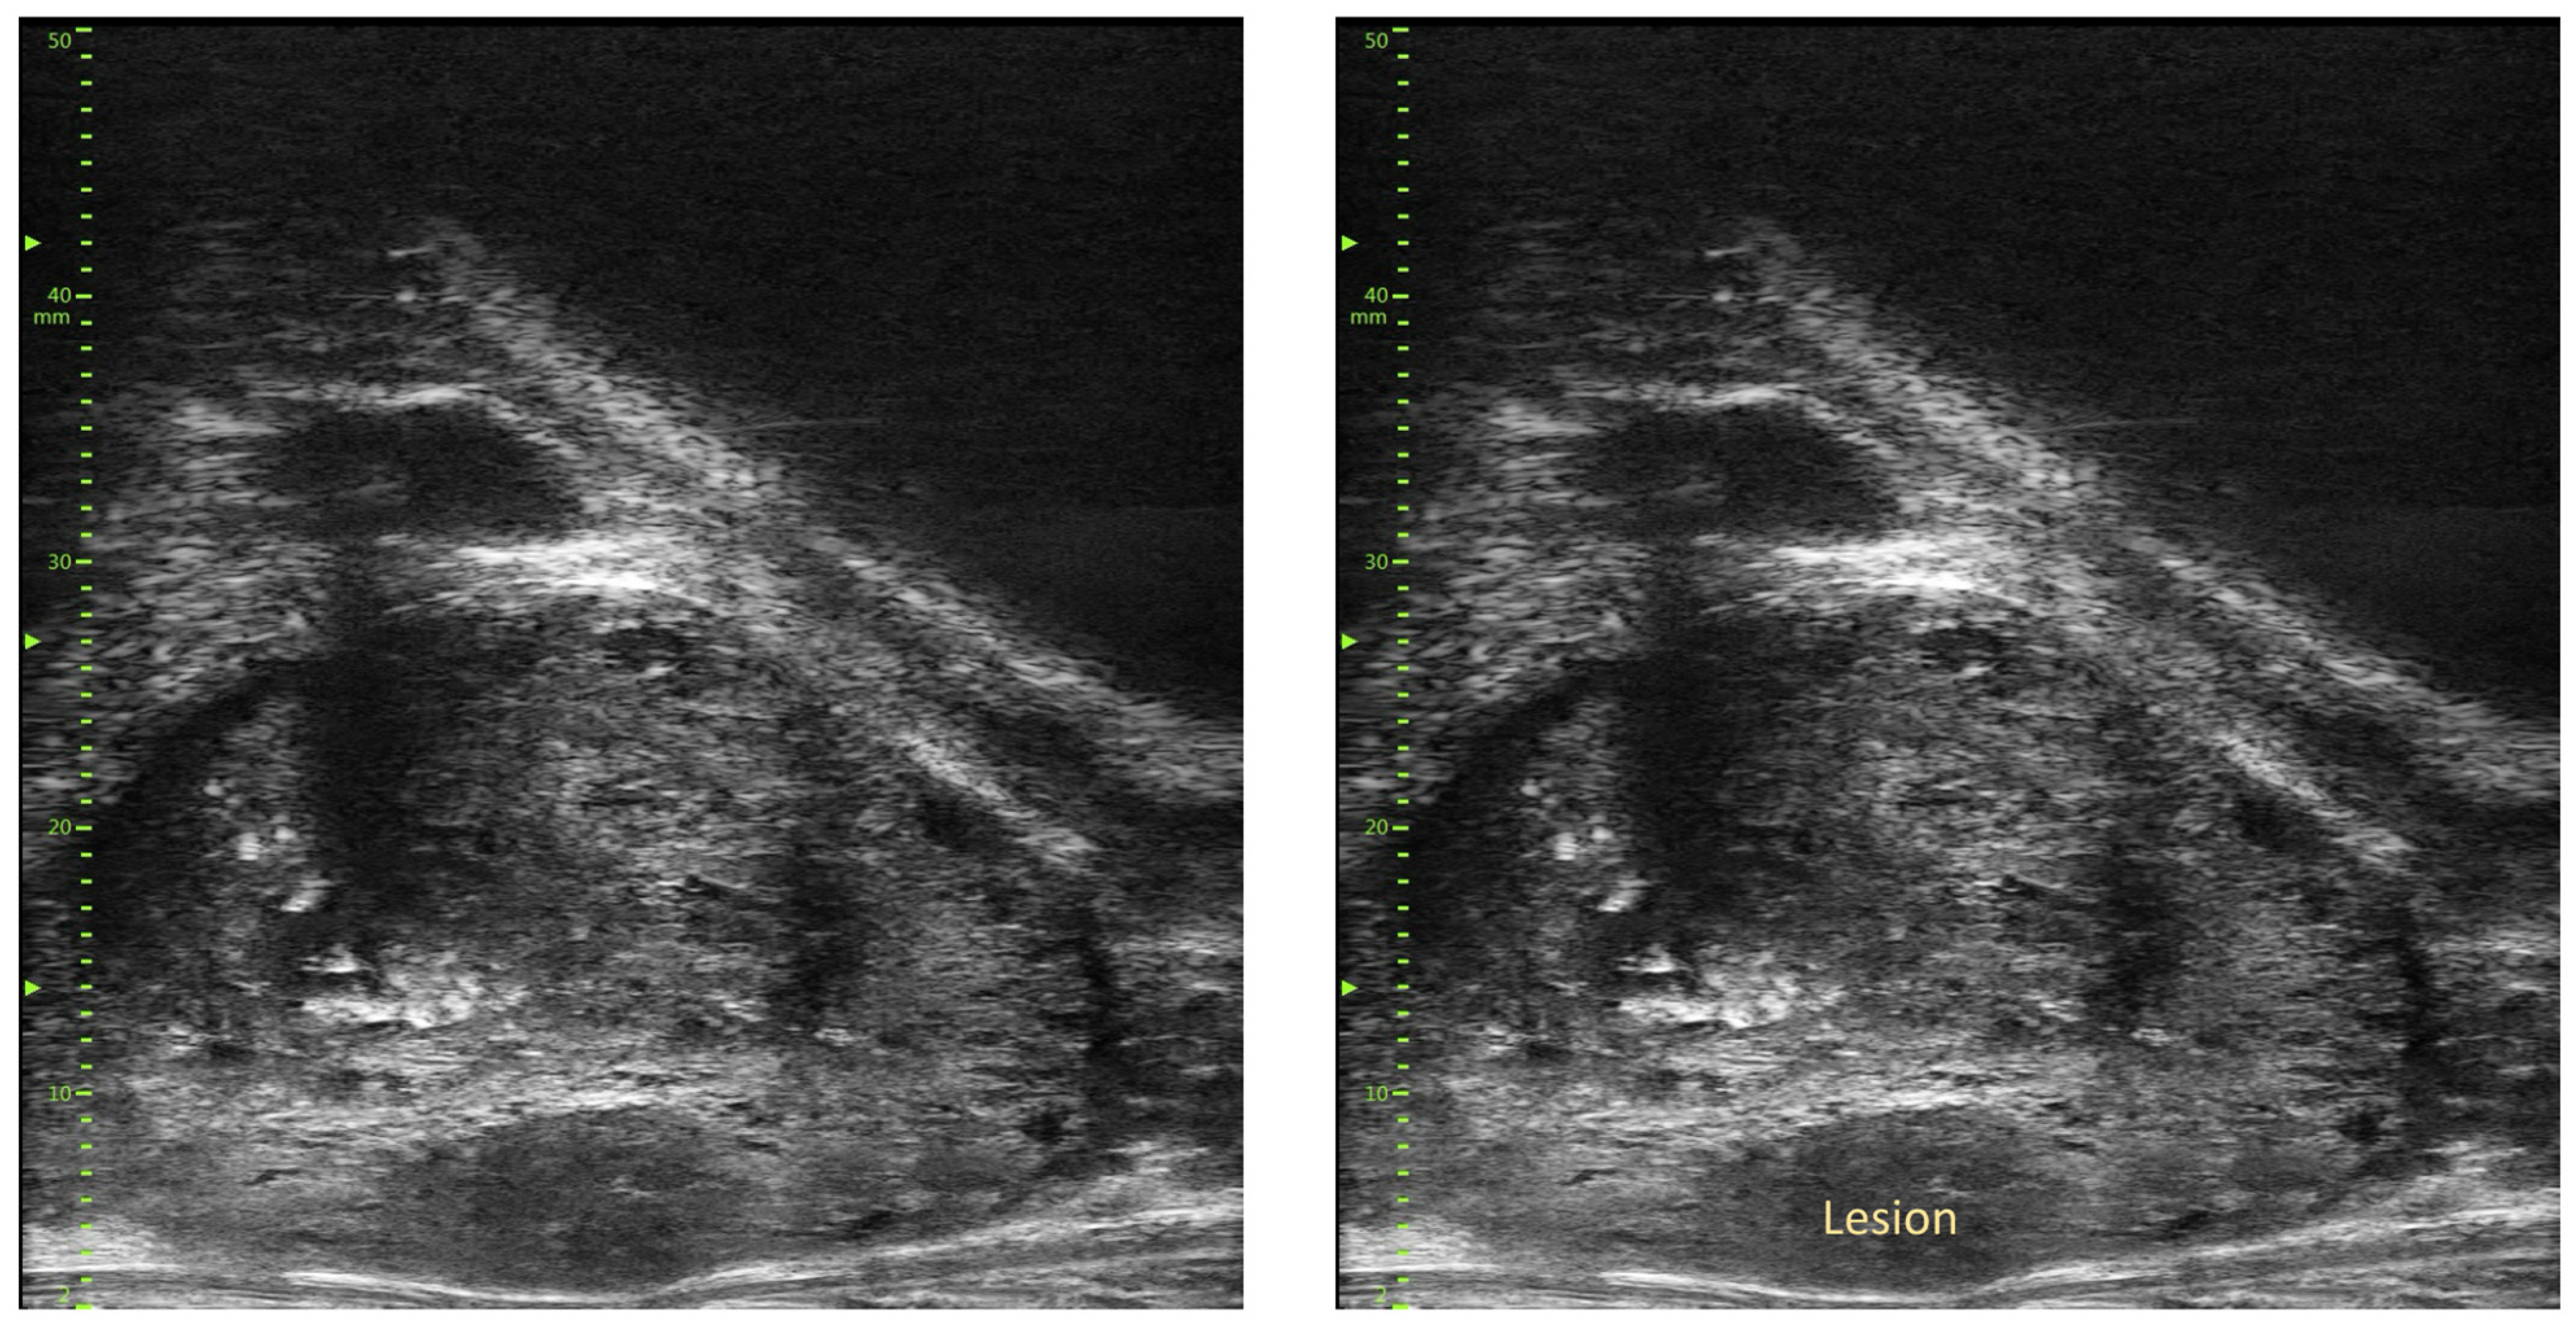

- Ghai, S.; Eure, G.; Fradet, V.; Hyndman, M.E.; McGrath, T.; Wodlinger, B.; Pavlovich, C.P. Assessing Cancer Risk on Novel 29 MHz Micro-Ultrasound Images of the Prostate: Creation of the Micro-Ultrasound Protocol for Prostate Risk Identification. J. Urol. 2016, 196, 562–569. [Google Scholar] [CrossRef]

- Abouassaly, R.; Klein, E.A.; El-Shefai, A.; Stephenson, A. Impact of using 29 MHz high-resolution micro-ultrasound in real-time targeting of transrectal prostate biopsies: Initial experience. World J. Urol. 2020, 38, 1201–1206. [Google Scholar] [CrossRef]

- Klotz, L.; Lughezzani, G.; Maffei, D.; Sanchez, A.; Pereira, J.G.; Staerman, F.; Cash, H.; Luger, F.; Lopez, L.; Sanchez-Salas, R.; et al. Comparison of micro-ultrasound and multiparametric magnetic resonance imaging for prostate cancer: A multicenter, prospective analysis. Can. Urol. Assoc. J. 2020, 15, E11–E16. [Google Scholar] [CrossRef]

- Pedraza, A.M.; Gupta, R.; Musheyev, D.; Pino, T.; Shah, A.; Brody, R.; Wagaskar, V.; Kaufmann, B.; Gorin, M.A.; Menon, M.; et al. Microultrasound in the detection of the index lesion in prostate cancer. Prostate 2024, 84, 79–86. [Google Scholar] [CrossRef]

- Ditonno, F.; Franco, A.; Manfredi, C.; Veccia, A.; Valerio, M.; Bukavina, L.; Zukowski, L.B.; Vourganti, S.; Stenzl, A.; Andriole, G.L.; et al. Novel non-MRI imaging techniques for primary diagnosis of prostate cancer: Micro-ultrasound, contrast-enhanced ultrasound, elastography, multiparametric ultrasound, and PSMA PET/CT. Prostate Cancer Prostatic Dis. 2023, 27, 29–36. [Google Scholar] [CrossRef]